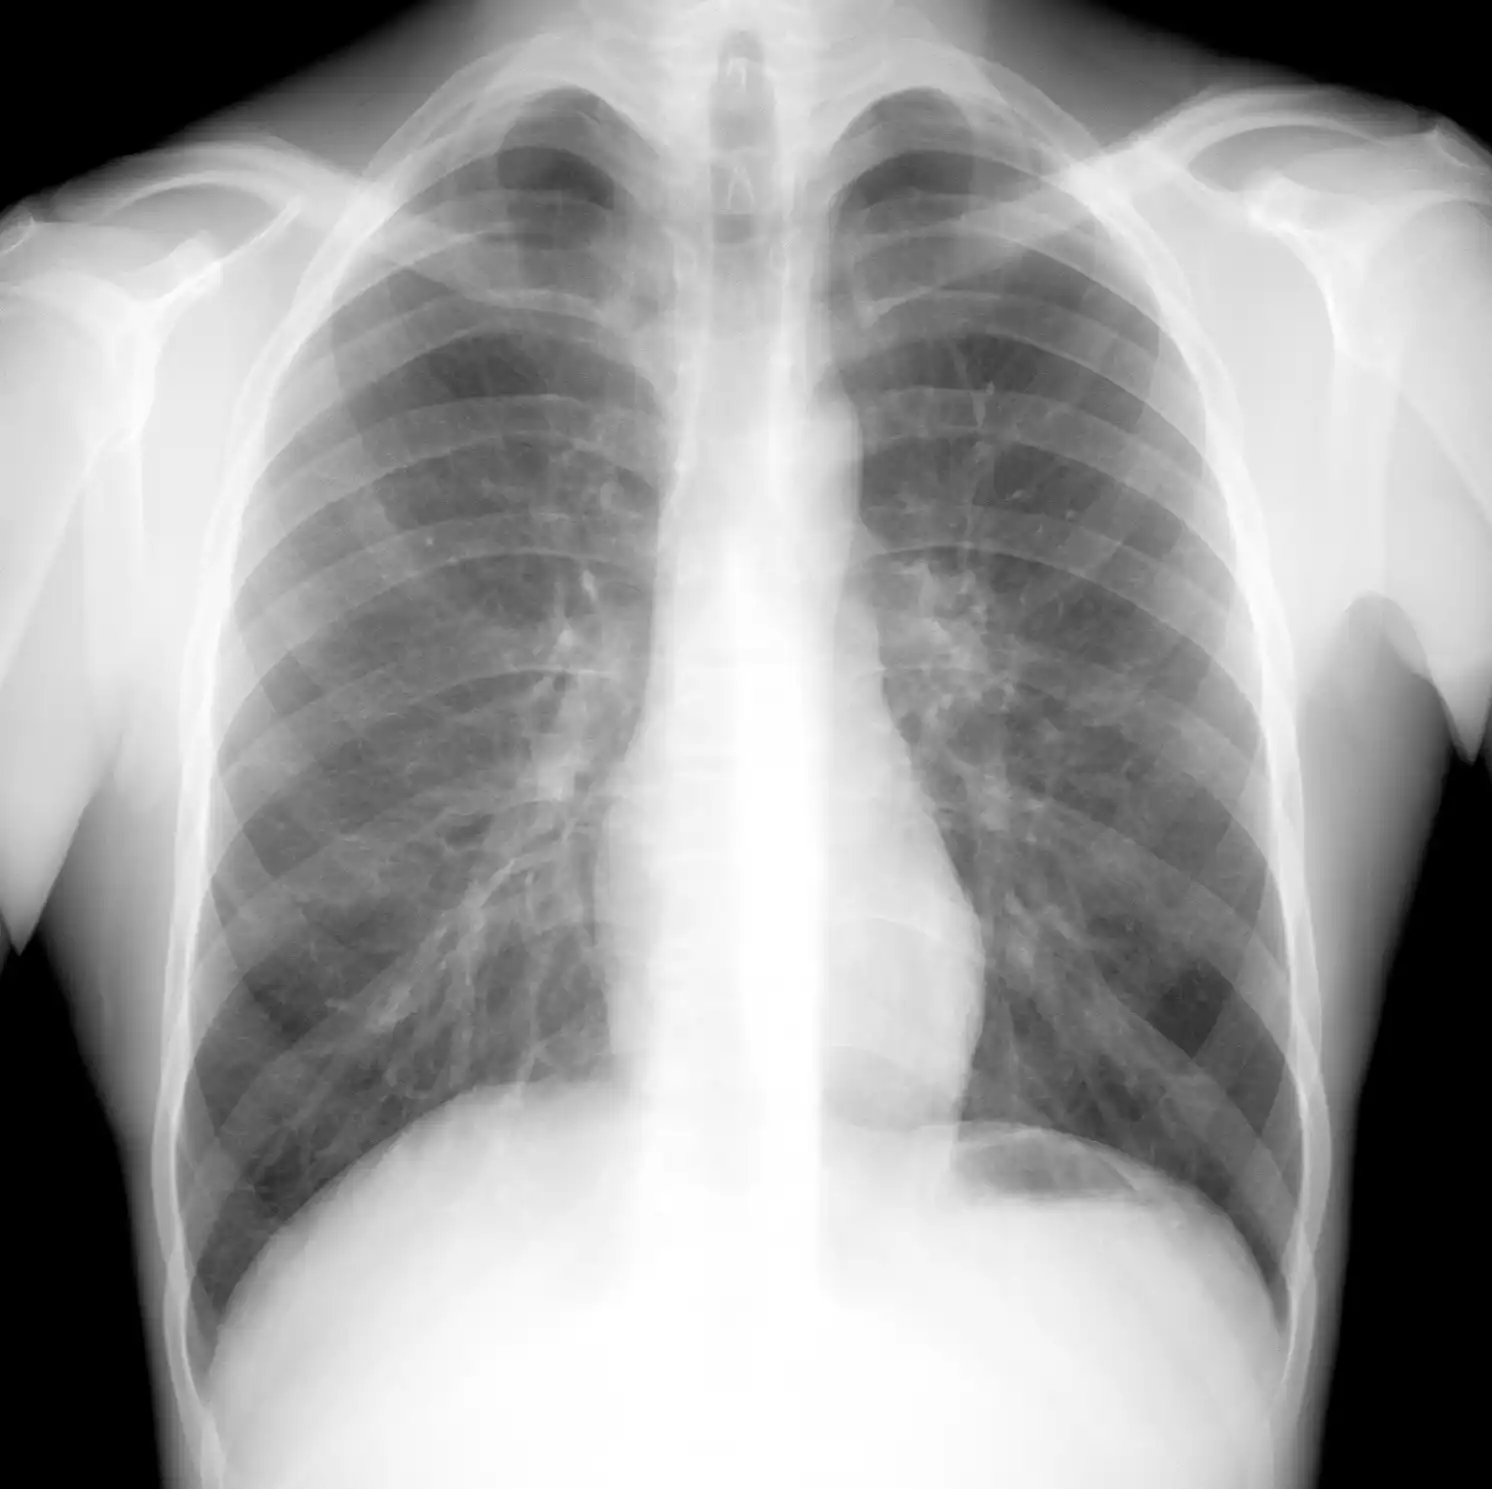

Рак легких в рентгеновском изображении

НОРМА: